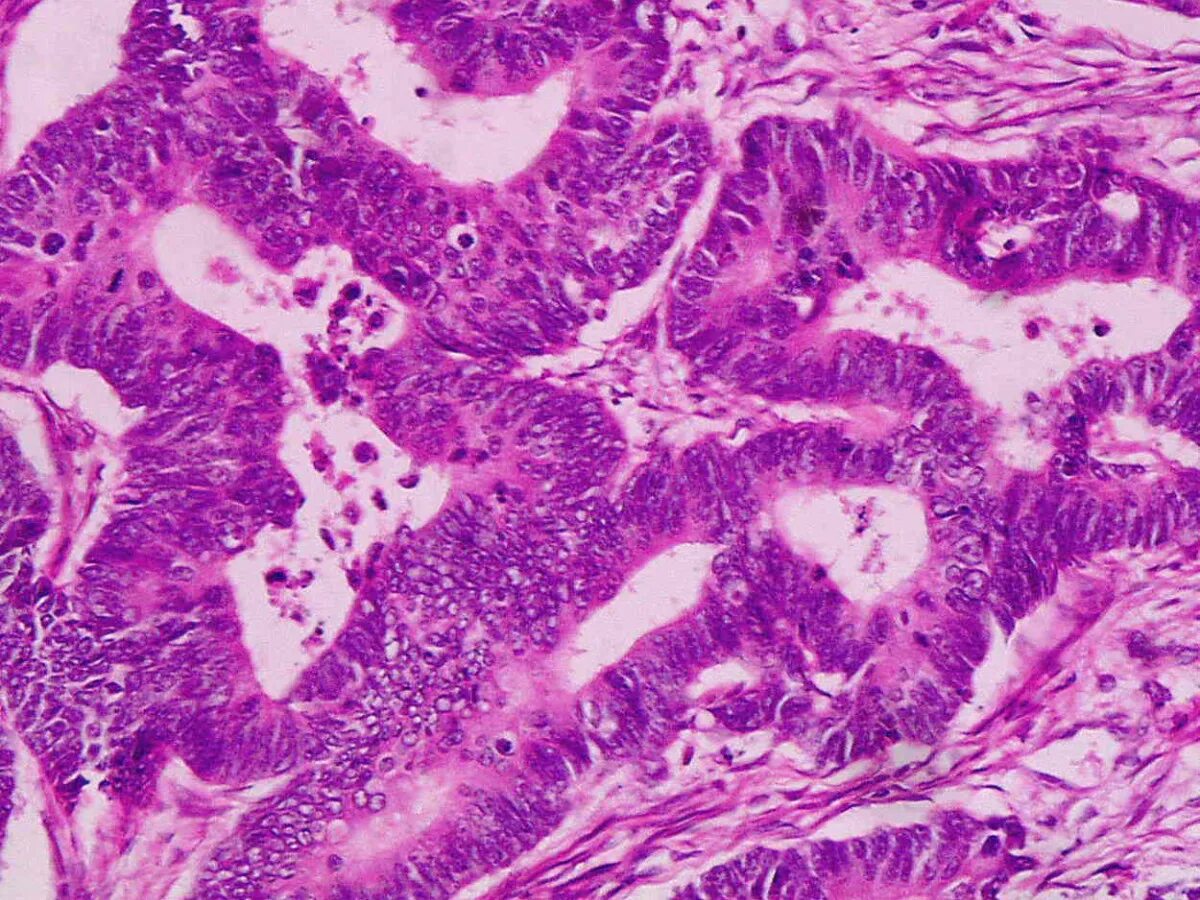

Высокодифференцированная аденокарцинома кишки